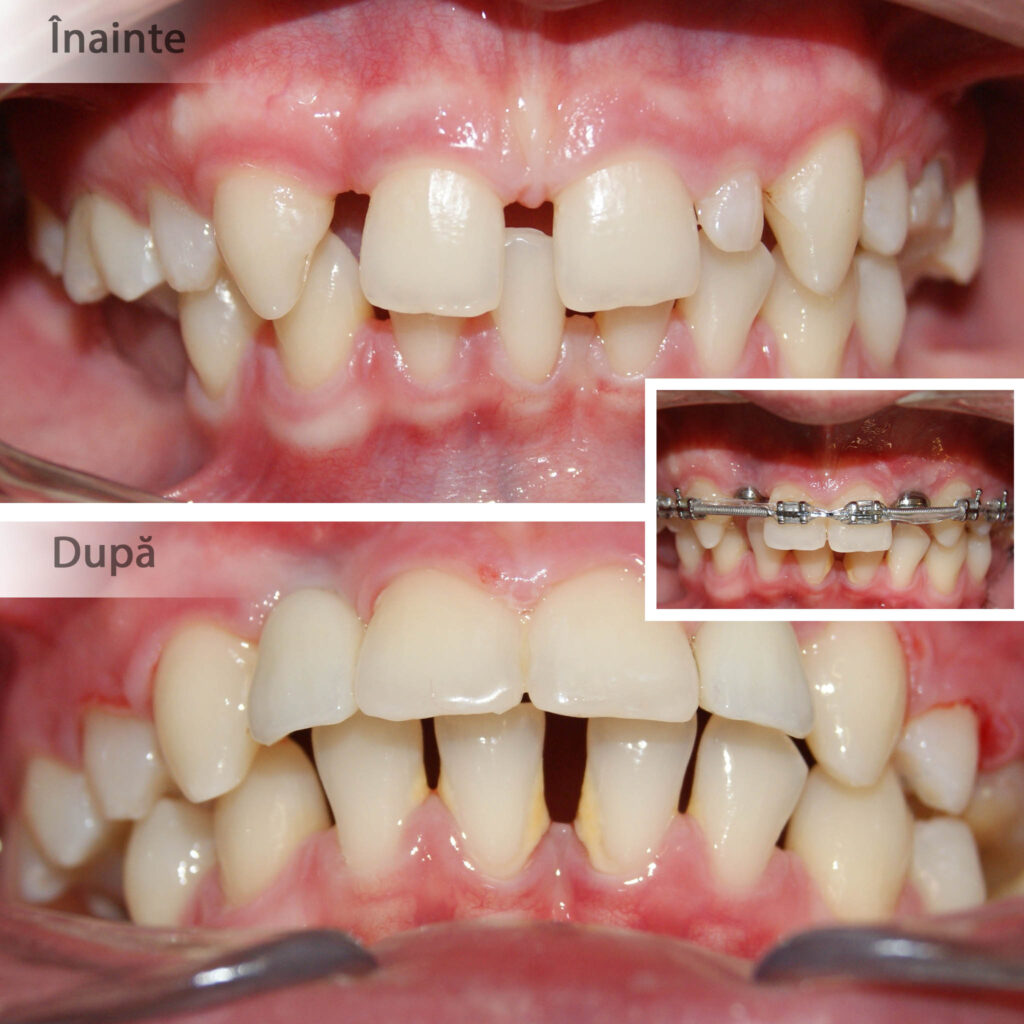

Adesea boala parodontală determină migrarea neplăcută a dinților. După încetinirea activității bacteriene dinții migrați pot fi readuși în poziție corectă